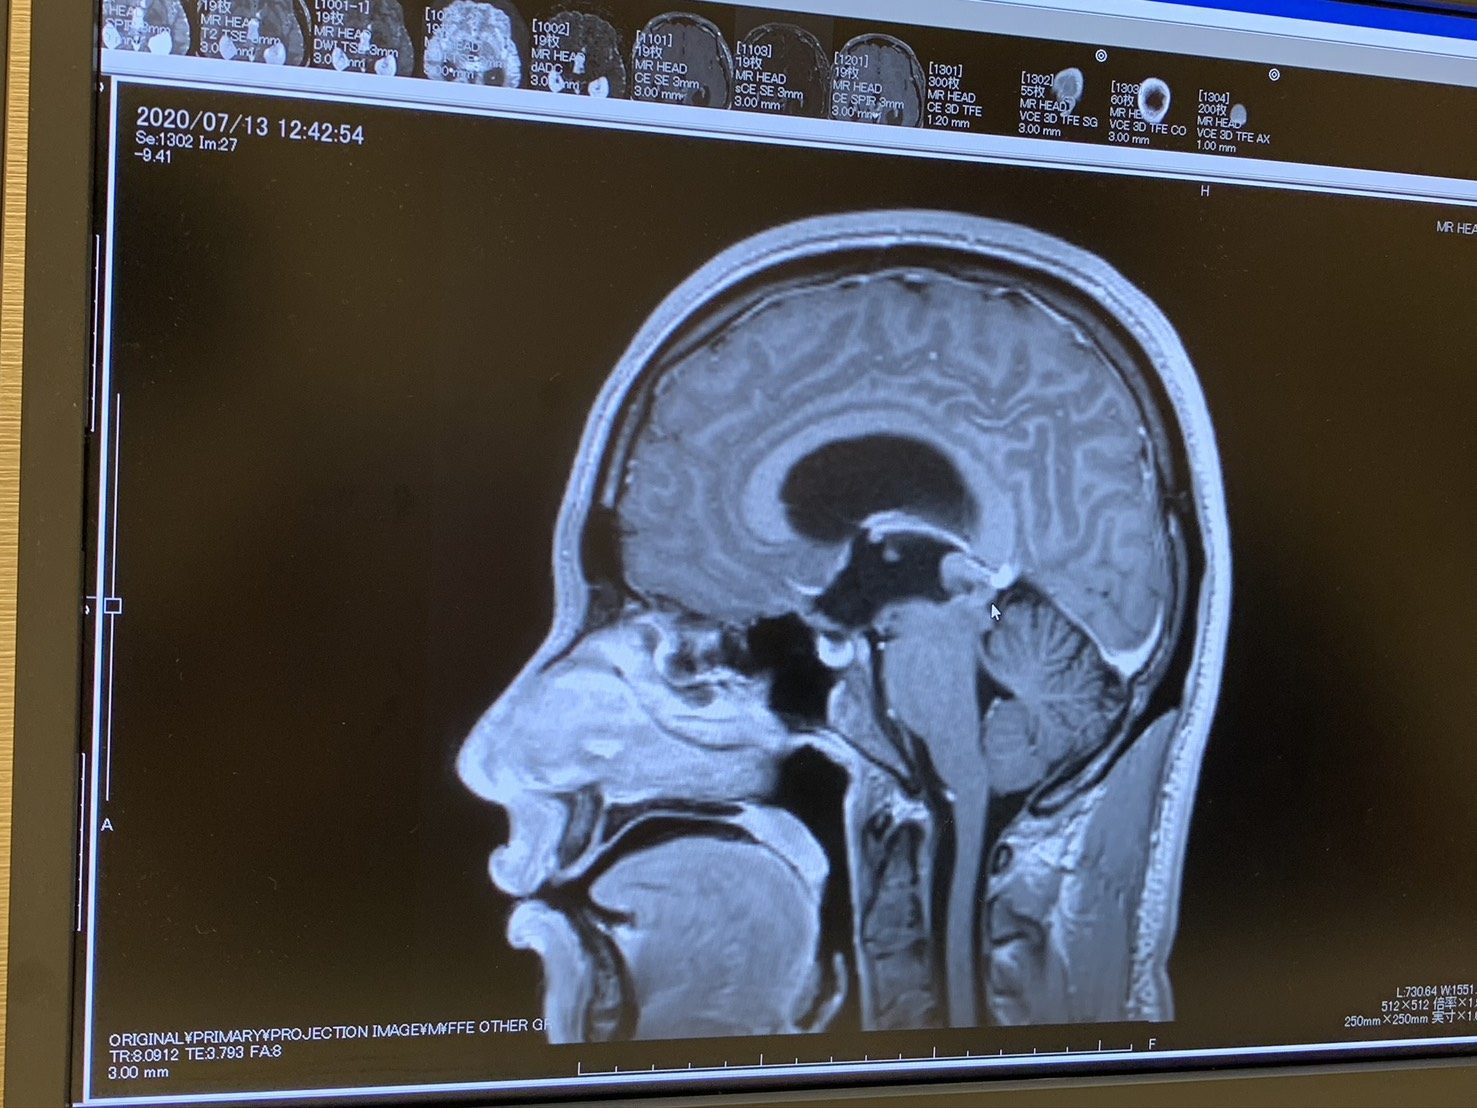

薬剤師として就職して約3ヶ月が経った2020年7月頃。@cancer.salonさんは、起床時の頭痛や吐き気、強い疲労感に加え、右を見るときだけ視界が歪むなど、体調の異変を感じるようになりました。

その後、職場の健康診断で「脳腫瘍の疑いがあります」と告げられ、精密検査の結果、緊急入院となり脳腫瘍と診断されます。診断と同時に手術、抗がん剤治療、放射線治療が決まり、本人の意思とは関係なく、物事が一気に進んでいく感覚でした。